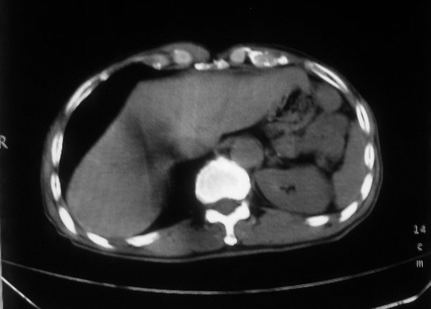

男,66岁,贲门ca术后一年,喝了5、6杯水了。怎么描述跟诊断啊